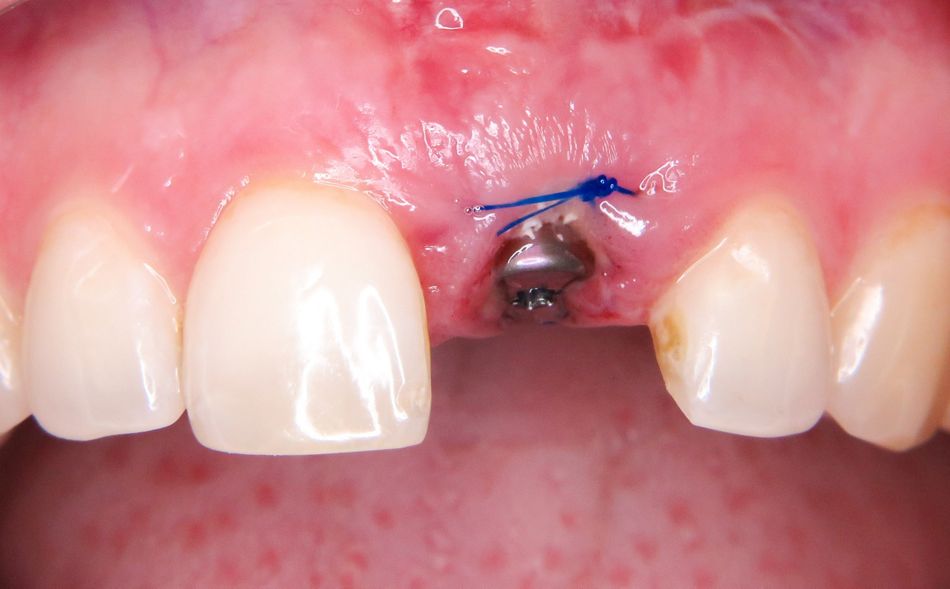

Extraktion und Insertion

Unter Lokalanästhesie wurde der beherdete Zahn 21 extrahiert und hierbei auf die maximale Schonung der vestibulären Lamelle geachtet. Die Entzündung konnte rückstandslos entfernt werden. Die Sondierung ergab eine intakte faziale Knochenlamelle (Abb. 6). Die frische Extraktionsalveole wurde als Implantatbett aufbereitet und das Implantat (BLX ø 4 mm, 14 mm) entsprechend der Planung dreidimensional im palatinalen Bereich der Alveole inseriert [3, 6] (Abb. 7 und 8). Das BLX-Implantat hat einige Besonderheiten im Design. So nimmt beispielsweise das Gewinde des Implantats zum krestalen Bereich hin an Stärke zu, sodass zusätzlich zur horizontalen Kondensation auch vertikal Knochen kondensiert wird. Ziel ist eine Primärstabilität im gesamten Implantatbett basierend auf einer homogenen Krafteinleitung. Drucknekrosen sollen so verhindert werden. Im krestalen Bereich ist das Implantat um 1/10 reduziert, um das sensible Gewebe in der Kortikalis drucklos zu lassen. Das BLX-Implantat konnte mit einer für die Sofortversorgung ausreichenden Primärstabilität (mind. 45 N/cm2) inseriert werden.

Der Spalt zwischen dem Implantat regio 21 und der vestibulären Alveolenwand (Jumping Distanz) wurde mit Knochenersatzmaterial (cerabone, Botiss) gefüllt (Abb. 13 und 14). Ziel einer Augmentation im Bereich der vestibulären Alveolenwand ist eine verbesserte Regenerationsfähigkeit der Hart- und Weichgewebe [15]. Um einen Kollaps der Weichgewebe zu verhindern, sollte die Alveole innerhalb kürzester Zeit versorgt werden. Der Resorption der bukkalen Lamelle soll durch die Augmentation bestmöglich entgegengewirkt und die Knochenneubildung unterstützt werden. Erfahrungsgemäß führt das Füllen des Gaps in vielen Fällen zu einem besseren Ergebnis. Aufwendige Folgeaugmentationen lassen sich oft vermeiden. Verwendet wurde in diesem Fall ein bovines Knochenersatzmaterial [4]. Nach dessen Einbringen und dem Aufsetzen der Abdeckschraube wurde die Situation mit einer Matratzennaht verschlossen (Abb. 15).